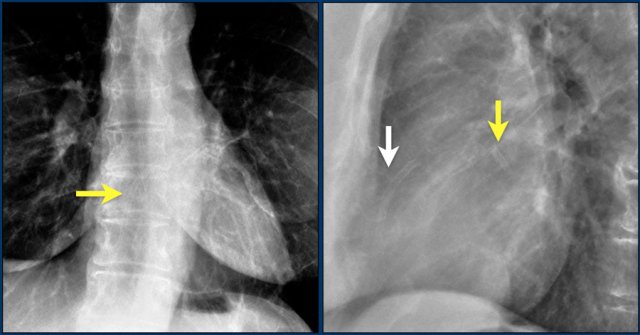

Here we see the normal valve position on an PA and lateral chest X-ray.

On the lateral chest film the aortic and pulmonary valves are located above the line from base of the heart to the apex and tricuspid and mitral valves are below this line.